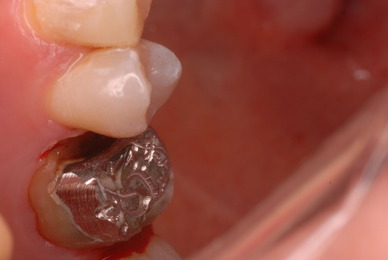

入れ歯の話から入りました。色々不満で注文があるようです。でも話が一段落して口腔内を調べると殆どの歯が重症で抜けそうな歯だらけなのです。

ご自分でやられても歯茎から血が出ないと話をされていましたが、私がブラシを当てると悲惨な状態であることがわかりました。